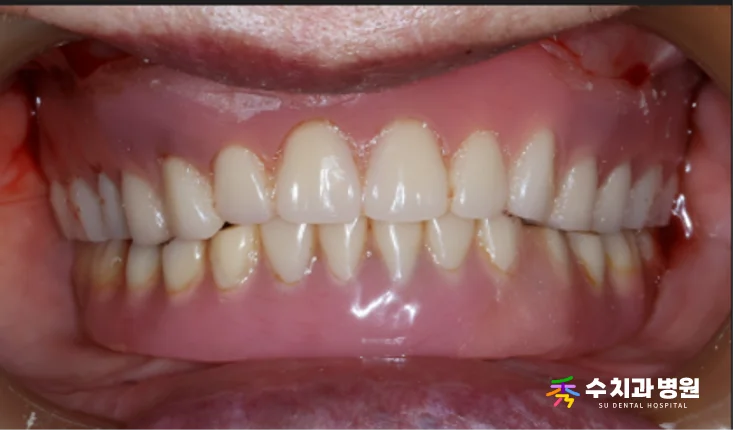

✨ 치료 후

최종 완전틀니를 장착하신 후,

저작 기능과 발음이 크게 개선되었으며

심미적으로도 자연스러운 모습으로 회복되었습니다.

[📸 치료 후 사진] (촬영일: 2025년 9월)